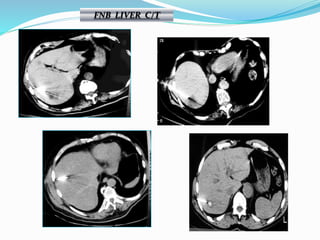

FNB LIVER U/S- C/T

FNB LIVER C/T